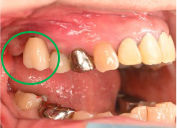

男性 Nさん 70代 (インプラント)

主訴

右下奥の歯が、グラグラして噛むと痛い。

治療内容

歯根の周りの骨が全く無い状態でしたので、保存することができず抜歯しました。3本歯がないところに2本インプラントを埋入しました。

所感

抜歯後、歯がなくなったところを補う方法には、部分入れ歯とインプラントがあります。この症例の場合、右下以外ほとんど歯が残っていますので、もし部分入れ歯にした場合、入れ歯のところで他のところと同じ感覚で噛むことができないので、慣れることが大変です。また部分入れ歯の支えになっている歯に負担がかかりますので、今後さらに歯を失う可能性が大きくなります。インプラントは、自分の歯と同じ感覚で噛むことができ、単独で植立していますので他の歯に負担がかかることがありませんので、更に歯を失うことを防ぎます。

インプラント2本:¥363,000×2本=¥726,000(税込)

ポンティック1本:¥115,500(税込)

合計:¥841,500(税込)

Before

※赤丸を抜歯しました。

After